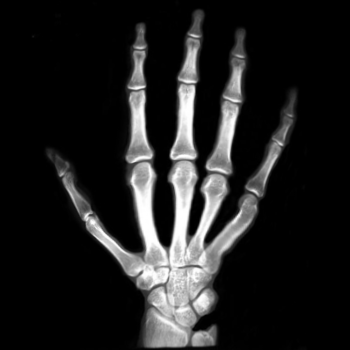

7.2. Real X-ray images

After testing our proposed method on several synthetic images, we now consider applying it on real medical images. Here, we consider a hand X-ray image as the source image (Fig. 7(a)) and a deformed hand X-ray image as the target image (Fig. 7(b)). Fig. 7(c) shows the original absolute intensity difference between the two images. It can be observed that different fingers are displaced in a nonuniform manner (for example, the displacement of the index finger is much larger than that of the little finger), while the wrist remains almost the same. Therefore, a simple rigid transformation is insufficient for yielding a good registration. As shown in Fig. 7(d), our proposed method successfully deforms the source image to match the target image, and the final intensity difference is significantly smaller (see Fig. 7(e)). From the deformed underlying grid in Fig. 7(f), it can be observed that the mapping is smooth and bijective. For comparison, both LDDMM [5] and DDemons [47] fail to register the fingers and are non-bijective (see Fig. 7(g), Fig. 7(h), and Fig. 7(i)).